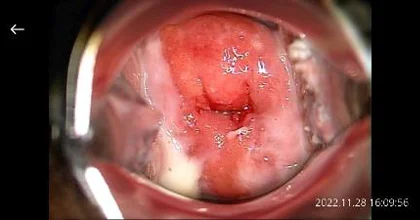

Анхдагч дэлгэцийг Зураг 13 (a)-д үзүүлэв. Зургийг томруулж харахын тулд зураг дээр дарах бөгөөд жижиг зурагны жагсаалт болон хажуугийн цэс алга болж Зураг 13 (б)-д үзүүлсэн дэлгэцэн дээр уг зураг гарч ирнэ. Энэ дэлгэцэн дээр хоёр хуруугаараа зургийг томруулж, жижигрүүлж үзэж болно.

Зураг 13 (a) - Цомог - анхдагч харагдац

Зураг 13 (б) - Зургийн харагдац Дэлгэц дээр дарснаар дүрсийг бүтэн дэлгэцээр харуулах боломжтой. Хоёр хуруугаараа томруулж, жижигрүүлнэ.